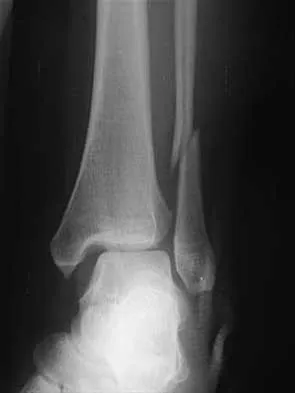

Question 33 High Yield

A 12-year-old boy with an ankle fracture undergoes closed reduction under sedation in the emergency department. Figure 27 shows a lateral radiograph of the ankle after two attempts at closed reduction. Based on these findings, treatment should now consist of

Detailed Explanation